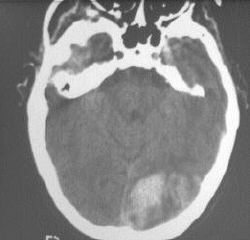

The two pictures (before and after treatment) were taken

about 20 years apart.

3. The following are true:

a. craniotomy scar is likely to be present

b. abdominal scar is likely to be present

c. if he fails to take his medication,

hypotension and hyperkalaemia will occur.

d. bitemporal hemianopia may be present

e. junctional scotoma may be seen